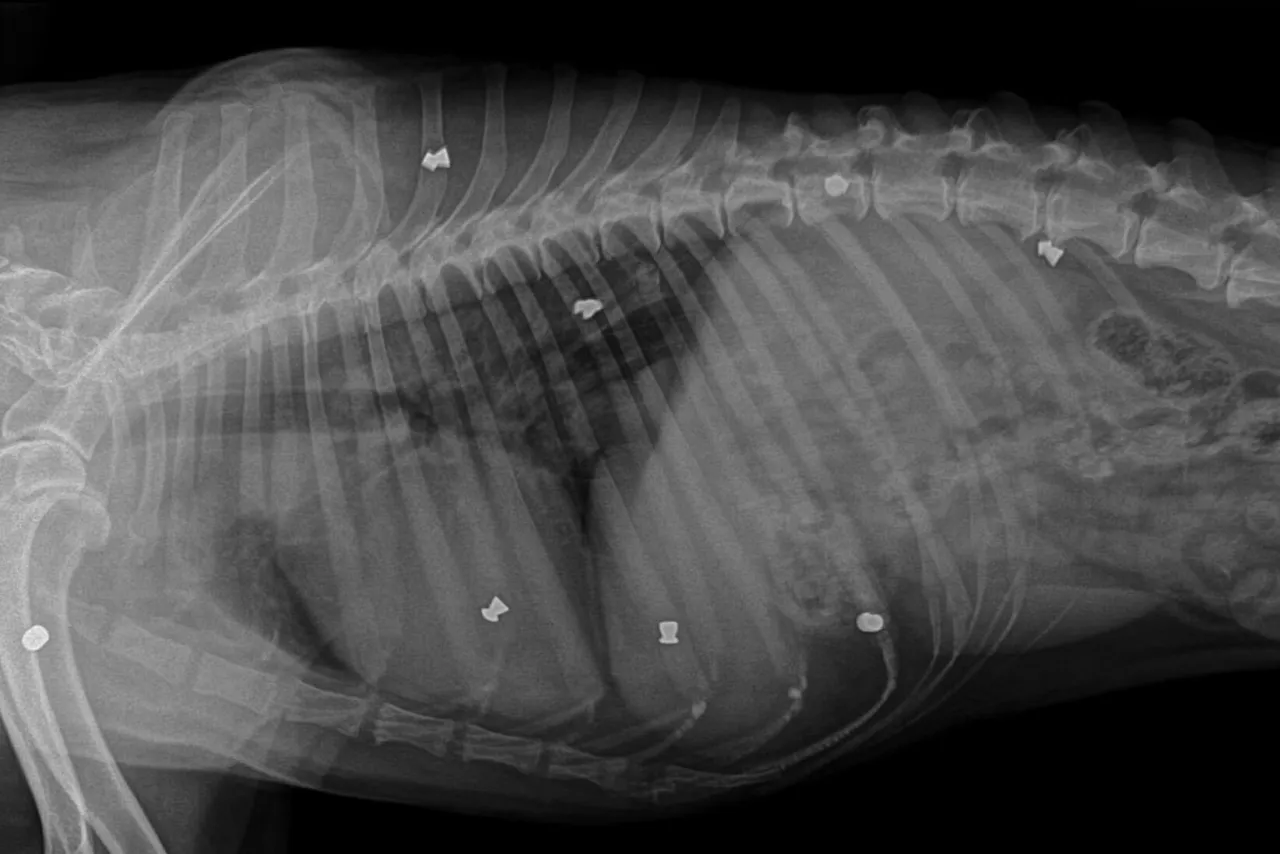

RTG klatki piersiowej psa: Ile kosztuje? Sprawdź ceny i wskazania

Dowiedz się, ile kosztuje RTG klatki piersiowej psa w Polsce, co wpływa na cenę, wskazania, przygotowanie i przebiegsprawdź nasz przewodnik.